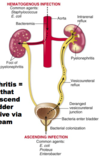

Acute Interstitial Nephritis

- Immune mediated hypersensitivity reaction to an antigen (e.g. drug or infection)

What do you see here?

Acute interstitial nephritis

What is the antigenic stimulus for AIN?

-

Antigens:

1. Tubular basement membrane

2. Secreted tubular proteins

3. Non-renal proteins (immune complexes) -

Immune activation via drugs or infectious agents:

1. As planted antigens

2. Acting as haptens to modify immunogenicity of native renal proteins

3. Molecular mimickery

4. Circulating immune complexes precipitation - NOTE: a hapten is a small molecule that can elicit an immune response only when attached to a large carrier such as a protein; the carrier may be one that also does not elicit an immune response by itself